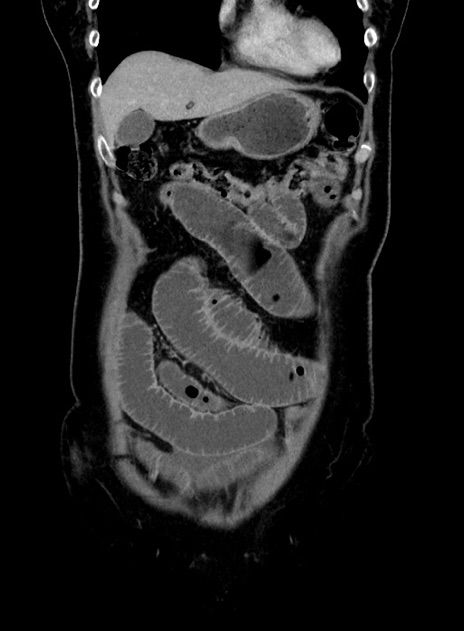

症例9(冠状断像)

【症例】 60歳代女性

【主訴】むかつき、みぞおちの痛み

【現病歴】3日前よりむかつきがあり、食事がとれない。

【既往歴】糖尿病

【身体所見】発熱なし、心窩部圧痛軽度あるも、腹膜刺激症状なし。

【データ】WBC 7400、CRP 1.92